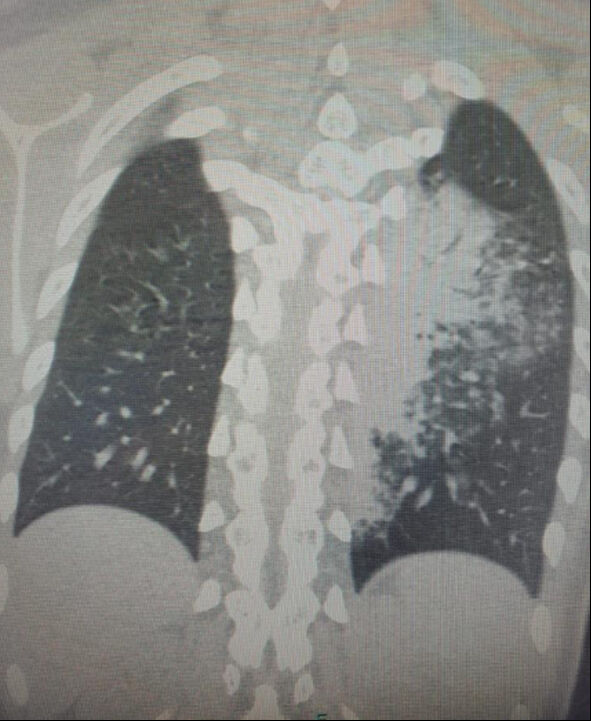

Göğüs Hastalıkları Uzmanı Prof. Dr. Şevket Özkaya, özellikle otel ve tatil köylerinde konaklayan kişiler arasında “beni klima çarptı” diyen neredeyse her iki kişiden birinde bu hastalıkların saptandığını belirtti. Prof. Dr. Özkaya, bu durumdan en çok etkilenenlerin ise çocuk yaş grubu olduğunu vurgulayarak, “Ciddi sayıda, daha önce görülmemiş derecede çocuk bronşiti ve zatürresi vakaları görmeye başladık. Hatta COVID-19 salgınında, çocuk yaş grubunda COVID-19 virüsüne bağlı bu kadar çok zatürre görmüyorduk. Son günlerde; ‘Legionella’ bakterisinin, çocuk yaş grubunda COVID-19’a oranla çok daha fazla zatürreye neden olduğunu görüyoruz” diye konuştu.

Legionella pneumophila isimli bakterinin klimalardan üremesi sonucunda hastalığın ortaya çıktığını belirten Prof. Dr. Özkaya, bu hastalığın kronik rahatsızlığı olanlarda ölümcül olabileceğini ve yaşlı, kronik hastalığı olan vatandaşların dikkatli olmaları gerektiğini hatırlattı.